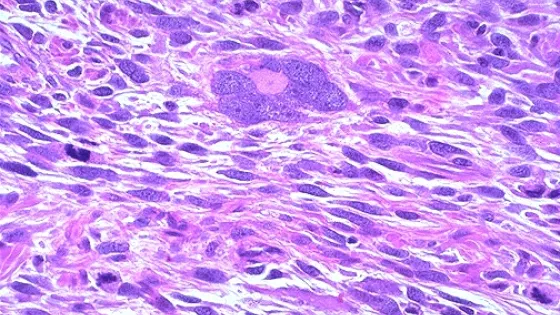

- Гистологический анализ подтвердил полное разрушение опухолевых клеток.

- Лейомиосаркома - агрессивная злокачественная опухоль мягких тканей.